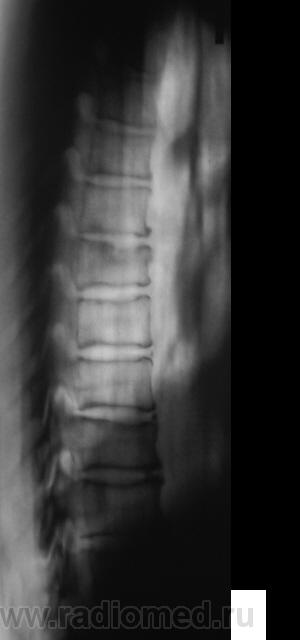

Если это женщина,старше 60 лет-обычная центральная грыжа Шморля при синильном остеопорозе.

Нет. Это мужчина. Возраст - 50 лет.

Тогда все равно грыжа Шморля :))))))))

Продольные полоски в телах позвонков тоже встречаю относительно часто. В книгах встречал 2 версии их происхождения: рудимент питающих артерий и форма перестроечной б-ни.

Похоже на большую грыжу, но мне кажется, что в ней что-то лежит, как сахарок тает? Не получится ли продолжения процесса?

Не в коем случае нельзя сбрасывать со счетов ТБС поражение позвонка. Создается впечатление о переходе процесса на вышележащий позвонок.

... тогда Фанарджяна (по костям) - в утиль! Какая перестроечная болезнь - во всех позвонках, строго по центру!?

Конечно же, рудимент. пит. артерии!